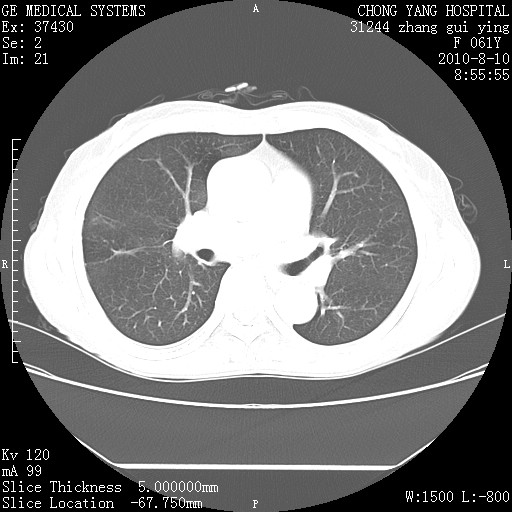

标题: CT28314:F61Y胸部增强,发热咳嗽一周入院,后面的为一周前平 [打印本页]

标题: CT28314:F61Y胸部增强,发热咳嗽一周入院,后面的为一周前平

1、支持考虑右侧中央型肺癌伴右肺中叶节段性不张及下叶支气管黏液痰栓    2、左肺上叶舌段感染。

支持3楼意见,还要考虑:纵隔及肺门淋巴结转移、右侧少量胸腔积液。

确切的说:1:右肺下叶中心型肺癌侵及中叶支气管并中叶不张,纵膈淋巴结转移。2:左肺舌叶炎症。3:右侧胸腔少量积液

1:右肺下叶中心型肺癌侵及中叶支气管并中叶不张,纵膈淋巴结转移。2:左肺舌叶炎症。3:右侧胸腔少量积液。支持!

右肺下叶中心型肺癌侵及中叶支气管并中叶不张,纵膈淋巴结转移。2:左肺舌叶炎症。3:右侧胸腔少量积液